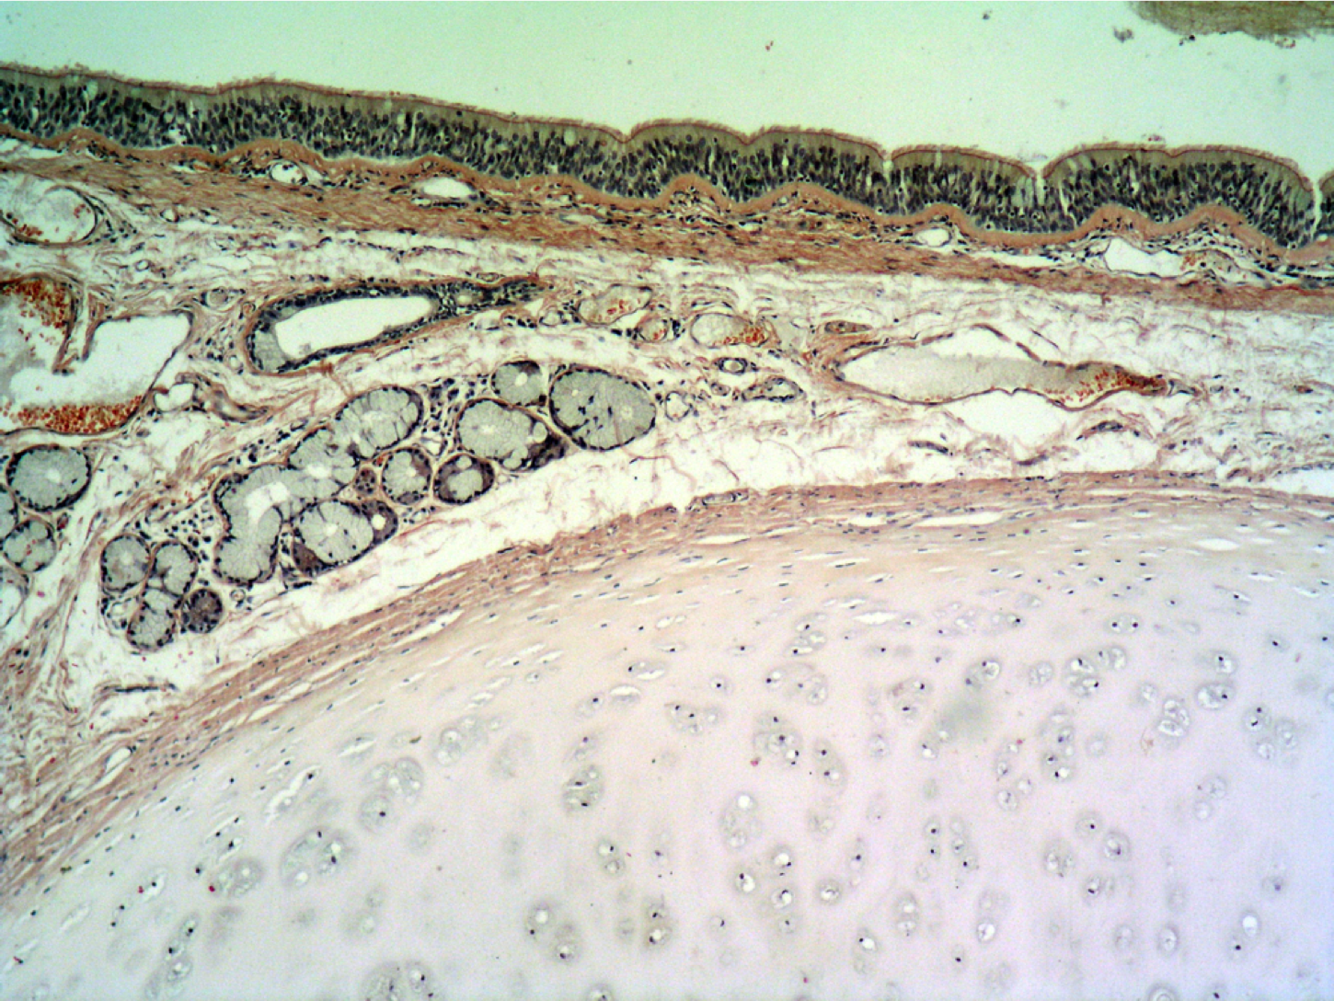

Identify

Pseudostratified Columnar Ciliated Epithelium (aka respiratory epithelium)

From Human Trachea

Thick basement membrane (pink)

Connective tissue with glands and rings made of hyaline cartilage